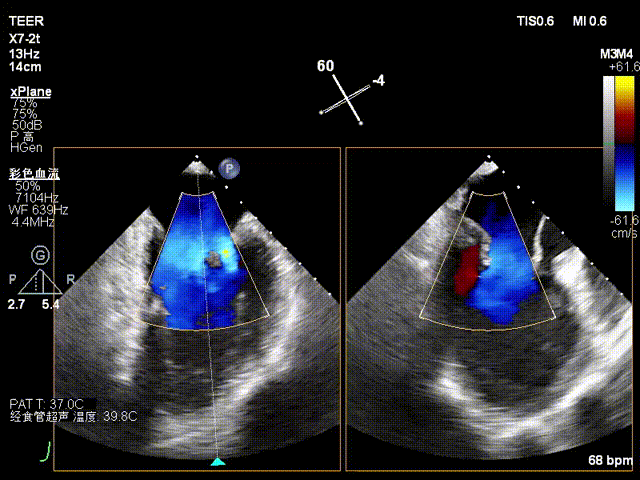

术前影像

X-plane2区彩色

X-plane 2区彩色